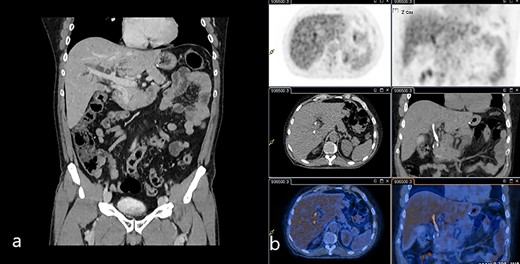

Abdominal US showed diffuse dilatation of the biliary tree. Magnetic resonance imaging and magnetic resonance cholangiopancreatography highlighted a 6-cm-long concentric thickening of the MBD below the biliary confluence towards the papilla of Vater (Fig. 1). Staging computed tomography (CT) showed no signs of lung or liver metastases (Fig. 2a). During percutaneous cholangiography, biopsies were performed, and a percutaneous internal-external drainage left in place to palliate jaundice. An 18-Fluorodeoxyglucoose Positron emission tomography (18-FDG-PET/CT) confirmed a slight uptake at the thickening of the MBD (Fig. 2b). Oncological markers, carcinoembryonic antigen and carbohydrate antigen 19-9 were not elevated.

(a) Venous phase of the CT scan showing the dilated biliary tree and the contrast-enhanced thickening of the common bile duct. (b) 18-FDG-PET/CT scan showing the slight uptake of marked glucose along the common bile duct.